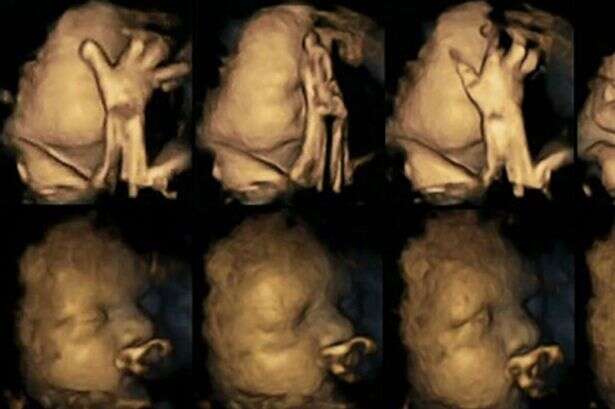

ההשפעות של עישון על ילדיכם ידועות, אבל ישנה קבוצה של מדענים שמאמינים כי הם יכולים להציג את ההשלכות של עישון עוד במהלך ההיריון. חוקרים עשו שימוש בטכנולוגיית D4 באולטרסאונד על מנת לייצר תמונות של עובר לאישה מעשנת. רופאים רבים מפצירים בנשים בהריון להפסיק לעשן בשל העלאת הסיכון ללידה מוקדמת, בעיות נשימה ואפילו מוות בחלק מן המקרים. כעת, מקווים החוקרים שהתמונות הללו יעודדו אימהות שנאבקות להפסיק לעשן.

ד"ר נדיה רייסלנד עשתה שימוש בטכנולוגיה מתקדמת על מנת לנהל רישומים של מאות תזוזות של עוברים ברחם. היא עקבה אחר 20 אימהות בבית חולים במידלסבורו, אנגליה. ארבע מהאימהות עישנו מספר ממוצע של 14 סיגריות ביום. לאחר שבחנה את סריקות התמונות שיצאו בשלבי ה-24, 28, 32 ו-36 שבועות להריון, היא גלתה שהעוברים של האימהות המעשנות נגעו בעצמם והזיזו את פיהם באופן מובהק, הרבה יותר מהעוברים של האימהות הלא מעשנות.

עוברים בדרך כלל נוגעים בעצמם ומזיזים את פיהם, אך ככל שהם גדלים הם גם הולכים ונפטרים מזה ומפסיקים בתזוזות. המסקנה מהנתונים של המחקר היא שהעוברים לאימהות מעשנות לא הפסיקו את תדירות התזוזות, דבר המצביע על היעדר התפתחות של המערכת העצבית. ד"ר רייסלנד מדגישה: "צריך להרחיב את המחקר בכדי לאשש את התוצאות שלו".

החוקרת מאמינה שההבדלים בין התצלומים, שמראים הבדלים ברורים, יכולים לסייע לאימהות להפסיק לעשן. עם זאת, היא מתנגדת לחלוטין להפוך אימהות שלא מצליחות לעשן לאנשים רעים והדגישה כי חייבים לעזור להם להפסיק ולתת להם תמיכה ראויה. למרות תוצאות המחקר כל התינוקות שהשתתפו בו נולדו בגודל ומשקל תקינים.

עמית המחקר של ד"ר רייסלנד, פרופסור בראיין פרנסיס אמר: "טכנולוגיה יכולה לסייע לנו לראות מה שהיה מוסתר, בכדי לחשוף כיצד עישון יכול להשפיע על התפתחות עוברים כל זאת בדרכים שלא האמנו, שיכולות להיות. תוצאות המחקר הזה הן הוכחה להשפעה השלילית של עישון על הריון".